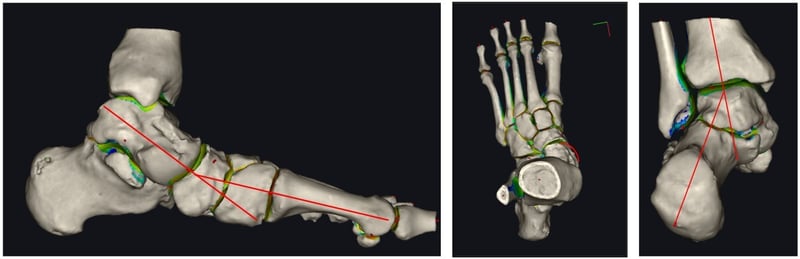

Ricostruzione in 3D di un piede piatto pre-intervento, con assi di riferimento per le deformità.

Nel mio personale planning chirurgico ritengo importante richiedere una proiezione radiografica, ideata dal collega Charles L. Saltzman, che si esegue in carico, da posteriore con inclinazione del raggio a 20 gradi.

Si tratta di una semplice radiografia effettuata in una posizione che consente di studiare meglio la correlazione tra la posizione del calcagno, dell’astragalo e della tibia. Aiuta a descrivere e studiare l’apice della deformità.